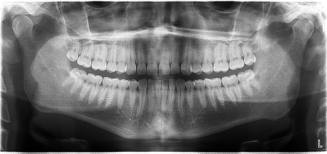

Před zahájením ortodontické léčby je nutné naplánovat léčebný postup. Při vstupním vyšetření si zakládáme dokumentaci k řádnému naplánování terapie. V této návštěvě si pacienta fotíme, otiskujeme horní i dolní zuby, zjišťujeme anamnézu a rovněž zhotovujeme rentgeny (opg a boční snímek lebky, případně rtg ruky).